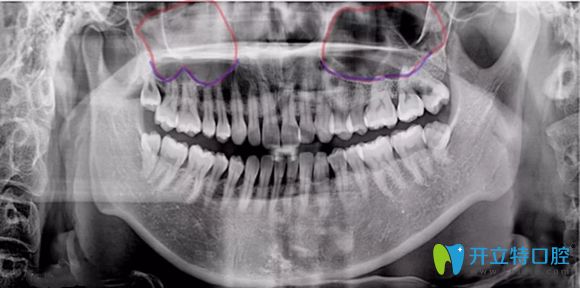

簡單來說,上頜竇提升術(shù)是由于患者上頜骨高度不足,使種植體不能有效埋入,固位不行,就需要增加上頜骨高度而產(chǎn)生的手術(shù)。主要分兩種方式及內(nèi)提升和外提升。

內(nèi)提升它是指不用做額外切口,就在種植體窩洞處,用敲擊法,或者是超聲骨刀磨除上頜竇底的骨質(zhì),使上頜竇底提升。同時植入骨粉,使牙槽骨的高度也增加,這樣就能使種植體可植入的長度增加,內(nèi)提升創(chuàng)傷較小,是臨床常用的方法。

外提升它適用于上頜骨高度極度不足,一般少于4mm,該情況下,可從上頜竇外側(cè)壁的骨板開窗打開上頜竇,剝離上頜竇底粘膜,植入骨粉來達(dá)到增加種植區(qū)域骨高度的術(shù)式。